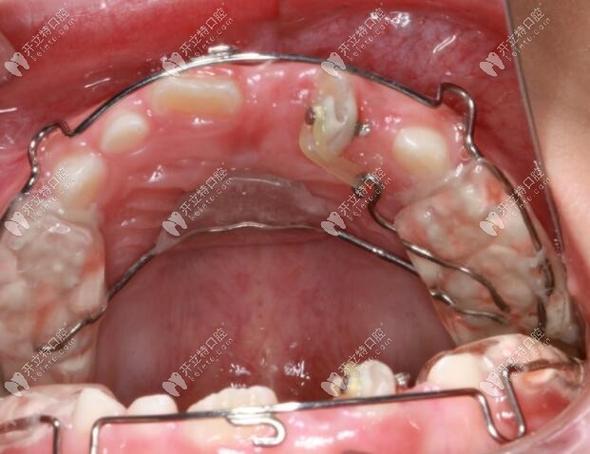

(图片来源网络,侵删)- 面诊: 正畸医生检查你的牙齿、咬合、面部比例、口腔健康状况。